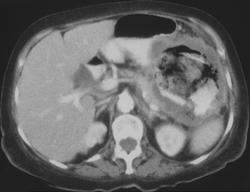

H. Pylori Simulates Gastric Cancer